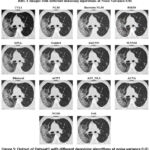

![]() |

Figure 4: Dataset1 and Dataset2 at different noise variances |

Figure 4 shows dataset 1 (HRCT) and dataset 2 (MRI) at four different noise variances (0.01,0.05,0.09, and 0.5).